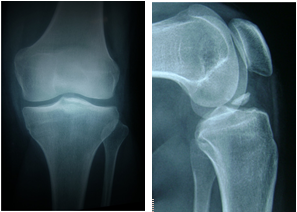

本组39 例,男28 例,女11例;年龄12-51 岁,平均26.3 岁。左膝22例,右膝17例。急性损伤25 例(伤后时间1-15 天,平均7 天),陈旧损伤14 例(伤后时间1月-7月,平均4个月)。受伤原因:损伤原因有摔伤、车祸伤以及膝关节扭伤。其中合并半月板损伤6例。依Meyers-Mckeever分型,II型29例、III型10 例,如图1示。

图1 前交叉韧带胫骨止点撕脱骨折,Meyers-Mckeever III型